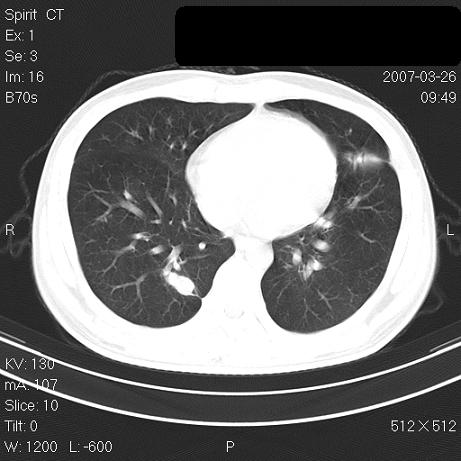

标题: CT7171B:补充治疗后2周复查

治疗后2周复查,请讨论

结合以前的ct片,还是考虑肺挫伤,吸收多了。

支持:创伤性湿肺。现肺挫裂伤(出血 积气)大部分吸收。建议继续治疗!

支持:创伤性湿肺、肺挫裂伤。现肺挫裂伤(出血、渗出、液气腔)大部分吸收。建议继续治疗!

经治疗后病灶明显吸收,考虑创伤性湿肺、肺挫裂伤